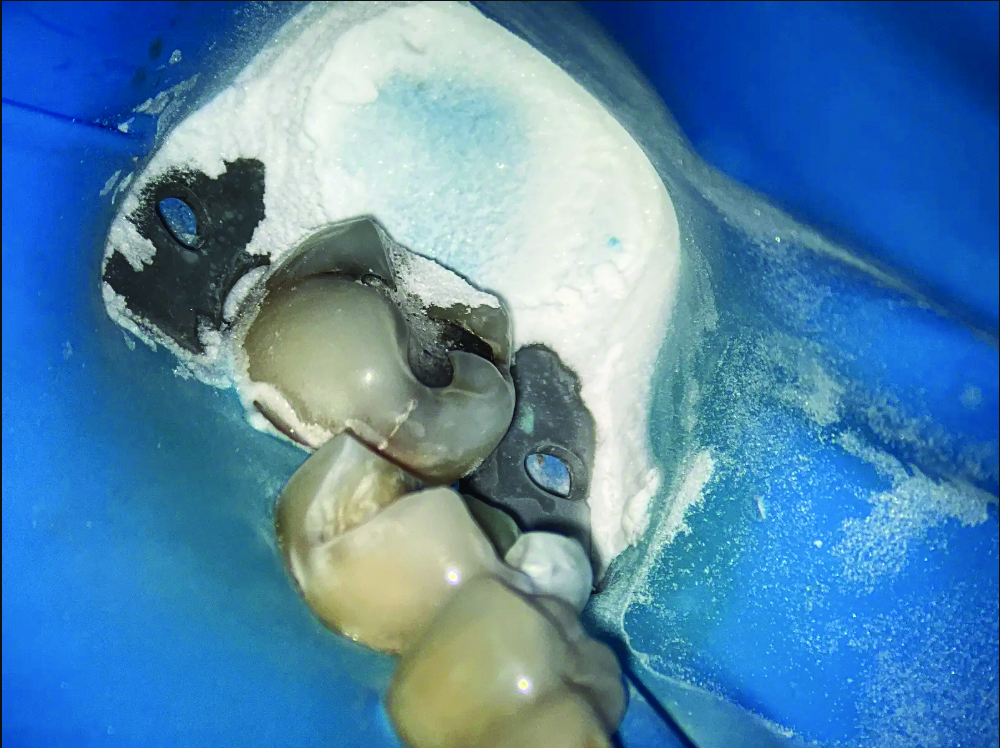

(4.) Intraoral images of a lower first molar before and after air abrasion to create a biobase. The accumulated aluminum oxide particles highlights the amount of abrasive used and the necessity of a rubber dam to prevent them from being inhaled or spread in the mouth.

Figure 4

(5.) Intraoral images of a lower first molar before and after air abrasion to create a biobase. The accumulated aluminum oxide particles highlights the amount of abrasive used and the necessity of a rubber dam to prevent them from being inhaled or spread in the mouth.

Figure 5

Over the years, air abrasion has continued to evolve, but aluminum oxide remains one of the most reliable abrasives used in practice today. Although alternatives such as bioactive glass have been explored, aluminum oxide is still the preferred choice because of its hardness and consistent cutting ability, especially when working on enamel and dentin.11 Unfortunately, the fine particles released during air abrasion can become airborne, posing risks such as soft-tissue irritation or inhalation. To address concerns related to airborne particles, newer air abrasion devices have been developed with water spray functions. These improvements help reduce the amount of dust and debris floating around in the air. In addition, the water stream makes the abrasive jet more visible, which helps the operator accurately follow its direction and point of contact. Furthermore, the addition of water helps to prevent excessive heat buildup in the tooth. Despite these advancements, it is still crucial to use isolation techniques, such as rubber dams, and to rely on high-volume suction to keep the work area clean and safe (Figure 4 and Figure 5).